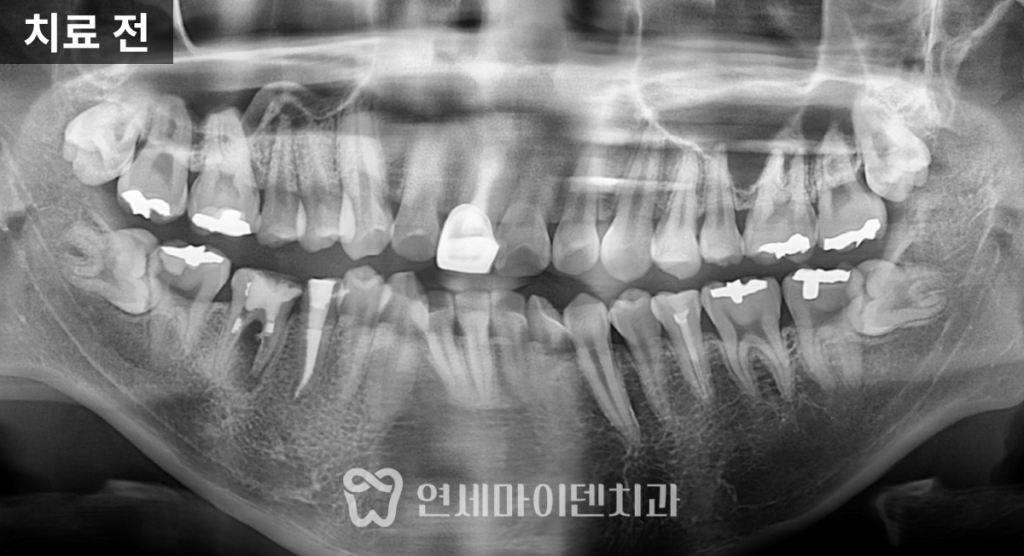

초기 검사 결과,

앞니가 전반적으로 앞으로 뻐드러져 있었고

일부 치아는 신경치료가 불완전하거나

염증이 동반된 상태였습니다.

발치 교정 치료 계획

일반적으로 돌출입 교정 시에는

송곳니 뒤쪽의 4번 치아 발치를 가장 많이 고려합니다.

하지만 이번 케이스에서는

다른 치아를 발치하는 방향으로 계획을 세웠습니다.

발치 기준은 다음과 같았습니다.

- 신경치료가 불완전하고 예후가 좋지 않은 치아

- 뼈 흡수와 염증 소견이 동반된 치아

이에 따라 오른쪽 아래는 큰어금니(6번),

오른쪽 위와 왼쪽 아래는 5번 치아,

그리고 교합의 대칭을 맞추기 위해

왼쪽 위 역시 5번 치아를 발치했습니다.